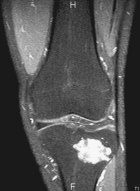

Case 4

16 year old male c/o 9 months of left knee pain

Zoom image: Radiological image Radiological image.